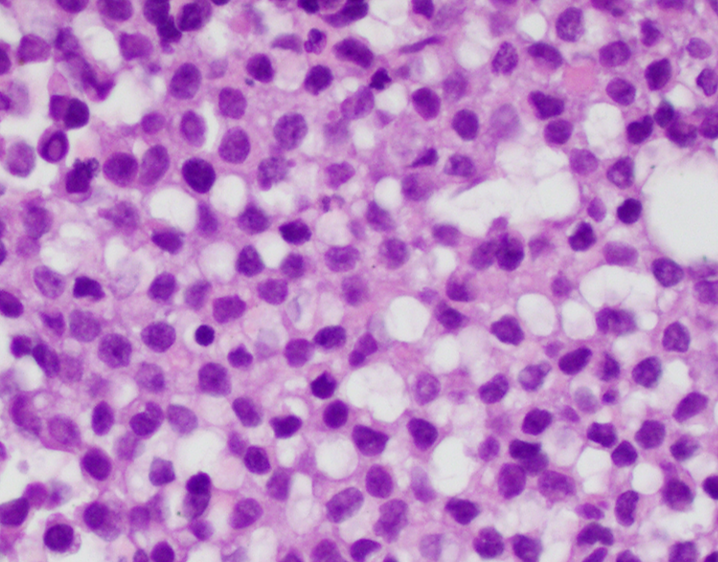

- Adamantinoma-like Ewing sarcoma (Head Neck Pathol 2020;14:59, Am J Surg Pathol 1999;23:159, Am J Surg Pathol 2015;39:1267)

- Nests of basaloid cells

- Peripheral palisading and cording

- Prominent myxoid, fibromyxoid or hyalinized stroma

- Focal keratin pearl formation

- High grade features with minimal pleomorphism

Microscopic (histologic) images